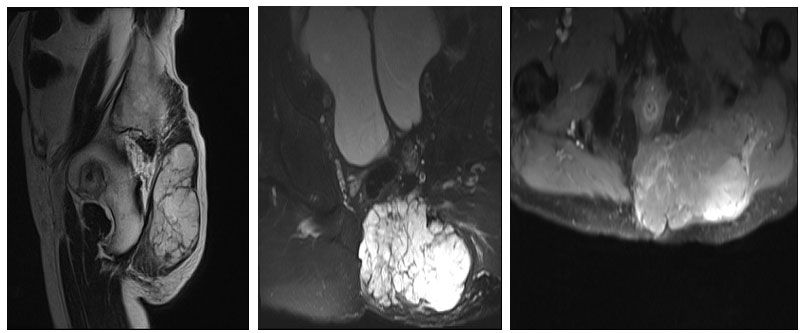

Ameliyat öncesi: MR’da kas içine doğru uzanım gösteren düzensiz sınırlı büyük tümör görüntüsü görülmekte